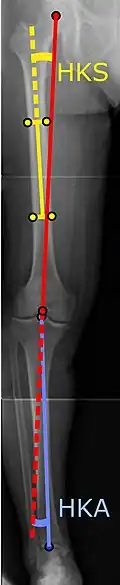

Angles commonly measured before knee replacement surgery: |

To indicate knee replacement in case of osteoarthritis, its radiographic classification and severity of symptoms both should be substantial. Such radiography should consist of weightbearing X-rays of both knees: AP, lateral, and 30 degrees of flexion. AP and lateral views may not show joint space narrowing, but the 30-degree flexion view is most sensitive for narrowing. Full-length projections also are used in order to adjust the prosthesis to provide a neutral angle for the distal lower extremity. Two angles used for this purpose are:

- Hip-knee-shaft angle (HKS),[14] an angle formed between a line through the longitudinal axis of the femoral shaft and its mechanical axis, which is a line from the center of the femoral head to the intercondylar notch of the distal femur.[16]

- Hip-knee-ankle angle (HKA),[15] which is an angle between the femoral mechanical axis and the center of the ankle joint.[16] It is normally between 1.0° and 1.5° of varus in adults.[17]